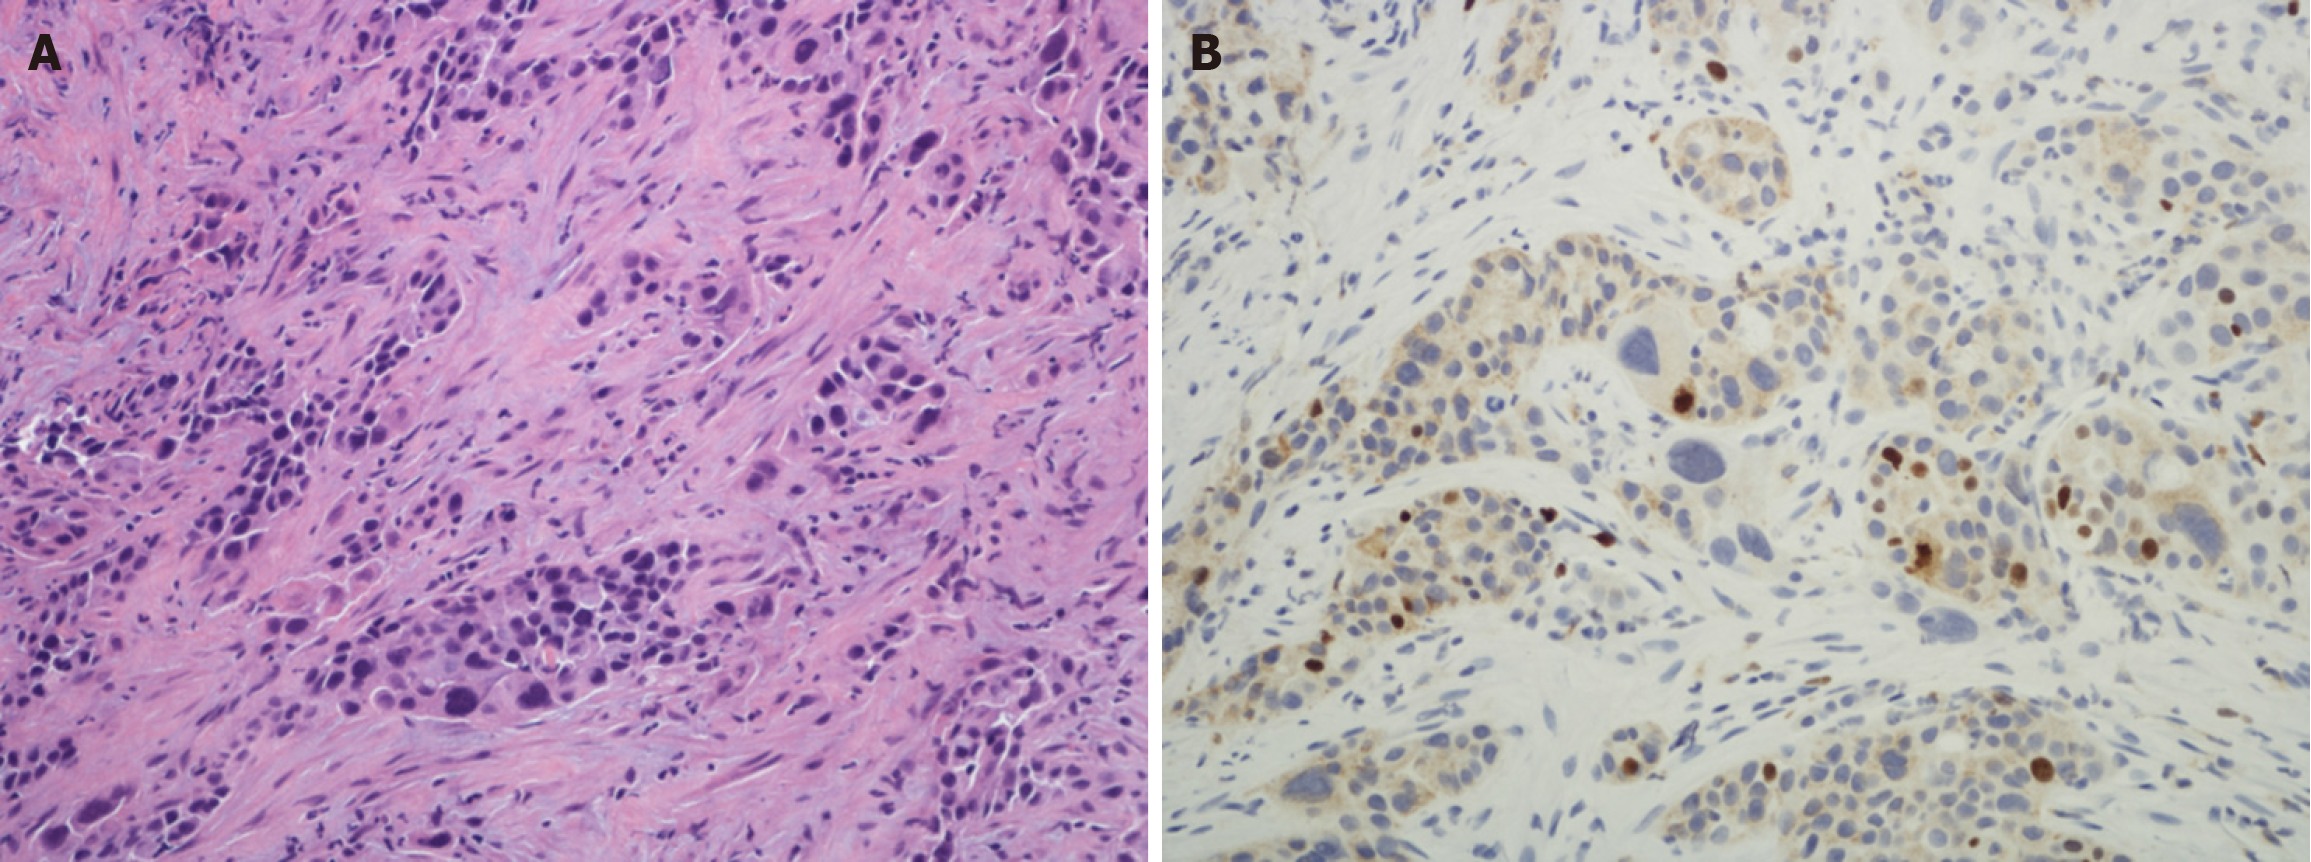

Figure 1 Photomicrographs of well-differentiated pancreatic ductal adenocarcinoma.

A: Low power view of fine needle biopsy that was obtained using endoscopic ultrasound. The glass slide showed > 2000 pancreatic ductal adenocarcinoma tumor cells which is very helpful for ancillary studies (original magnification × 20); B: Higher power view of one of the cores from Figure 1A showing a well-differentiated pancreatic ductal adenocarcinoma (the well-differentiated glands can be seen on the left and an islet of Langerhans on the right) (original magnification × 100).